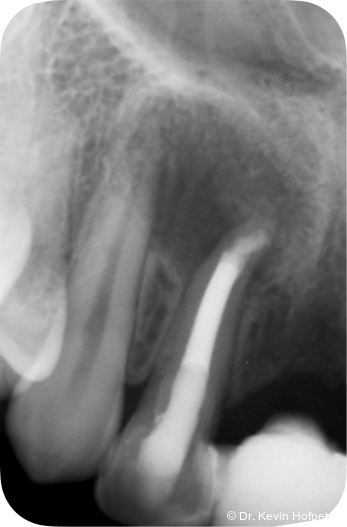

Klinisch zeigten sich die Zähne 12 und 13 karies- und füllungsfrei. Zahn 12 reagierte nicht auf Sensibilitätstests und war leicht perkussionsempfindlich. Zahn 13 reagierte unauffällig. Radiologisch zeigte sich eine ausgedehnte apikale Aufhellung am Zahn 12 sowie eine Hartgewebsformation im apikalen Kanallumen (Abb. 1–2d).

Geplant wurde eine Wurzelkanalbehandlung an Zahn 12. Die zunächst vorgesehene Zystektomie mit Wurzelspitzenresektion wurde zurückgestellt, um die Heilungstendenz nach orthograder Therapie zu beurteilen und einen chirurgischen Eingriff möglichst zu vermeiden.